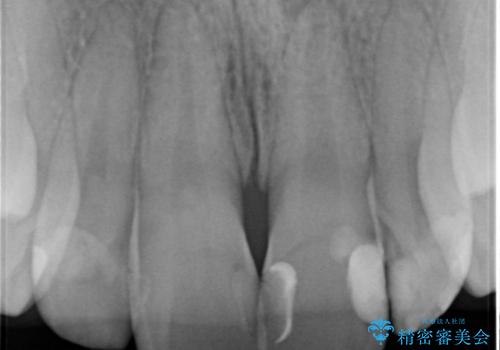

X線検査の結果、変色をきたしている歯は根尖病変が存在し、神経が失活している状態でした。

根管治療を行ったのち、セラミッククラウンで審美性を改善していきます。